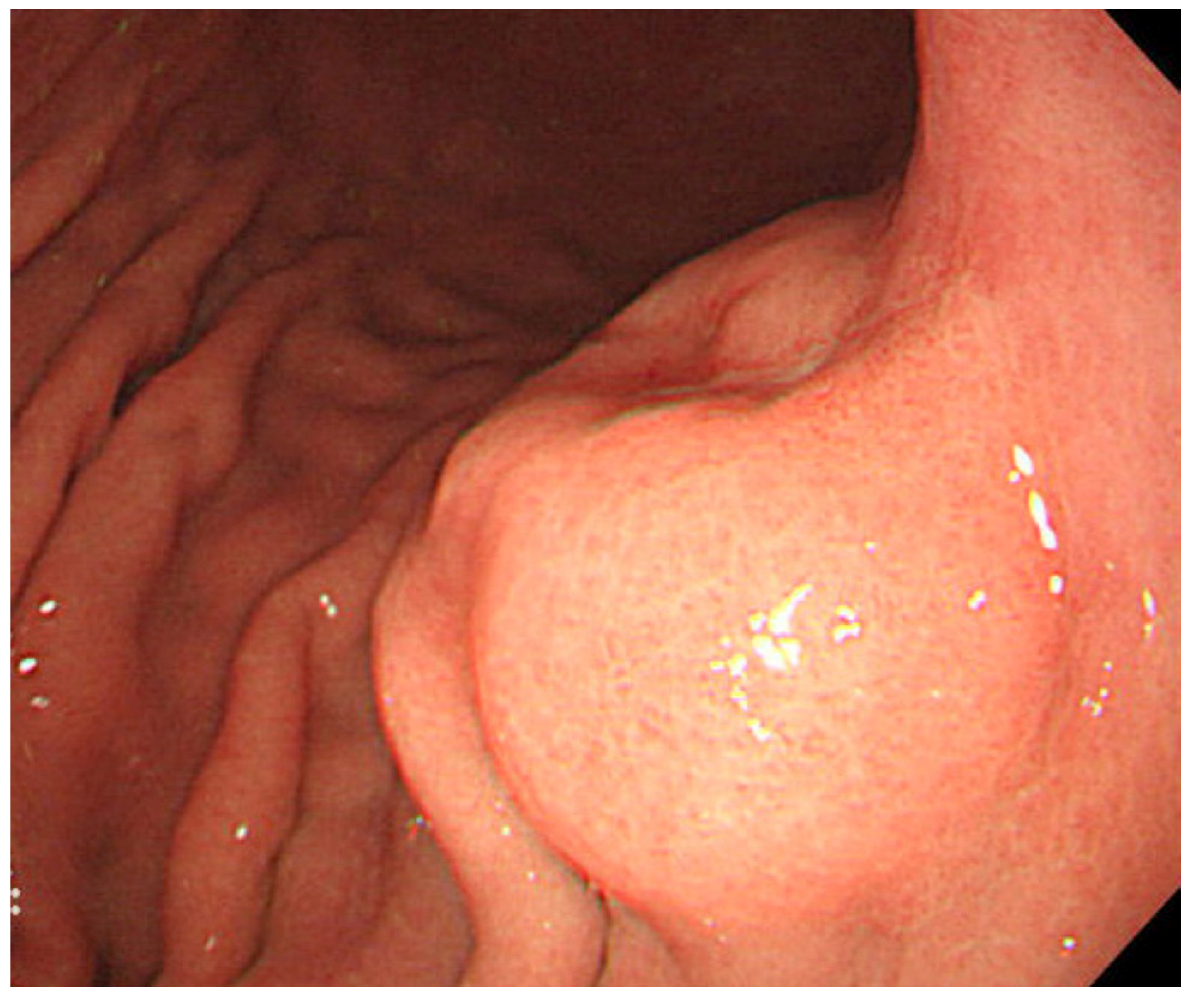

The most useful modality for the diagnosis of gastric carcinoma is endoscopy. By endoscopy, EBVaGC appears as superficial depressed (or ulcerated) lesions in the upper part of the stomach (Figure 2). Tumor locates predominantly in the non-antrum part of the stomach [19]. Because gastric cancer related to Helicobacter pylori (Hp), a causative agent of chronic gastritis, intestinal metaplasia, and cancer, locates predominantly in the antrum, these pathogens have been thought to cause gastric cancer by independent mechanisms [19]. Gastritis related to Hp frequently starts in the antrum. However, Yanai et al. reported that EBVaGC are frequently located near the mucosal atrophic border, where mild to moderate chronic atrophic gastritis (CAG) is common [24]. They also showed frequent detection of both EBV and Hp at the mucosa with moderate CAG, where inflammatory cell infiltration is abundant, and not at the mucosa with marked CAG, where inflammatory cell infiltration is scarce [25].

Figure 2.

Endoscopic image of an early EBVaGC in the upper gastric body. The tumor shows protruded shape probably because of the abundant lymphocyte infiltration.